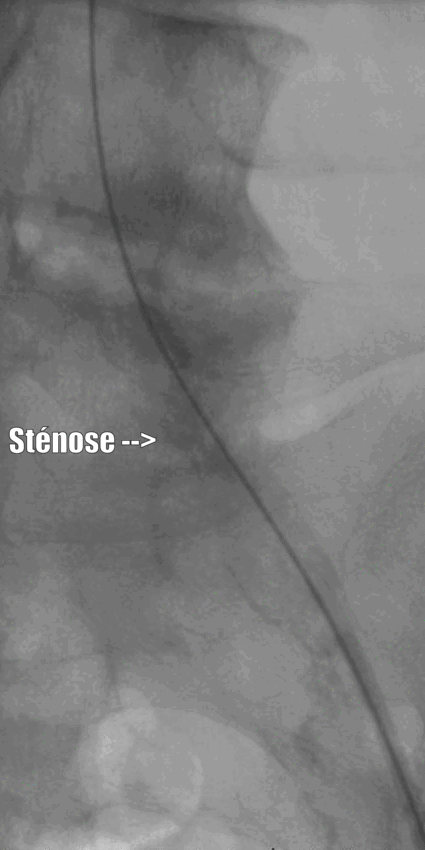

Au cours d’un hospitalisation courte (24h en règle générale), de façon mini-invasive, sous sédation douce et anesthésie locale (pas d’anesthésie générale) le radiologue passe par une artère du pli de l’aine, navigue dans les artères pour retrouver la sténose et la reperméabilise à l’aide d’un ballon et parfois d’un ressort (appelé «stent») qui sont positionnés dans les artères sous contrôle radioscopique (le radiologue visualise en temps réel la progression de ce matériel au sein de vos artères sur un écran).